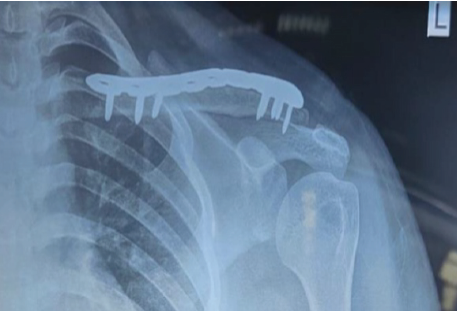

During the first 6 months of follow-up, the patient had no clinical symptoms or evidence of recurrence on X-rays done at monthly intervals and there was consolidation of the defect with no evidence of implant loosening or breakage (Fig. 8). Patient could perform all day-to-day functions with ease. Oxford Shoulder Score at 15 months post-procedure was 13 (minimum score 12).

Figure 8: X-ray left shoulder anteroposterior view – at 6 months follow-up.

A meticulous post-operative protocol with vigorous post-operative rehabilitation ensured an excellent post-operative outcome at 15 months follow-up (Fig. 9).

Figure 9: X-ray left shoulder anteroposterior view – at 15 months follow-up.